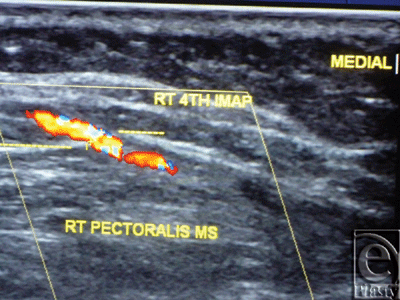

The site of the detectable perforator(s) was projected by a colored marker on the patient's skin so as to estimate the label remoteness (representing the perforation site) from the sternum (Fig 2), and the number of encountered perforators parasternally in each investigated space was counted as well. The inner diameter of each perforator was measured (Fig 3). Figures 4 to 8 show color duplex photos for perforators penetrating the fascia to reach the dermoglandular target.

| Figure 3. Color Duplex photo shows the diameter and depth of a certain visualized 5th internal mammary artery perforator from the skin surface. The point of measurement was at the perforation point. |

![]() |

| Figure 4. Color Duplex photo shows a 4th internal mammary artery perforator while perforating the superior surface of the pectoralis major muscle (the dashed line). |